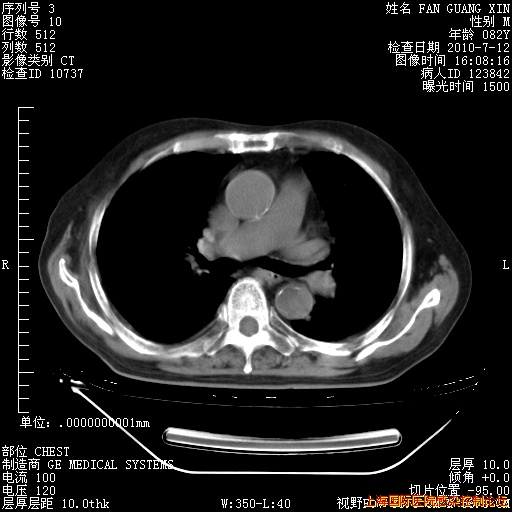

6月12日纵膈窗

整整相隔30天的肺部CT好像有所好转啊。甲强龙减量第3天,需要观察体温。

海管,自昨日你和我通完话后,不知您岳父消化道症状有无缓解?体温怎样?阅读7.12日胸部ct,个人认为目前激素治疗是有效的,甲强龙减量是适宜的。因在抗痨治疗,需密切观察肝功、肾功能和血常规。不过,老年、长期住院和大量使用激素,很担心菌群失调发生